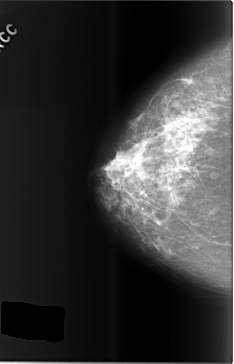

C_0504_1.RIGHT_CC

RIGHT_CC LINES 5824 PIXELS_PER_LINE 3736 BITS_PER_PIXEL 12 RESOLUTION 50 NON_OVERLAY